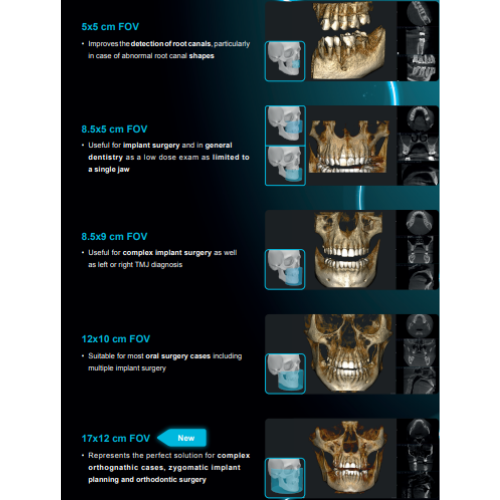

- Field Of View: 5x5, 8.5x5, 8.5x9, 12x10

- Adjustable FOV

- Large FOV